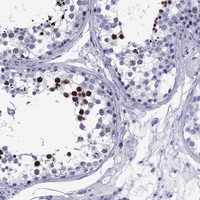

Immunohistochemical staining of human testis shows strong nuclear positivity in cells in seminiferous ducts.